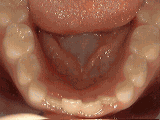

Deep overbite: Lower front teeth bite into palate

This adult patient, age 25, required braces and jaw surgery to correct his severe overbite, with treatment taking two years. His problem could have been corrected without surgery if he had been treated before he was a teenager.